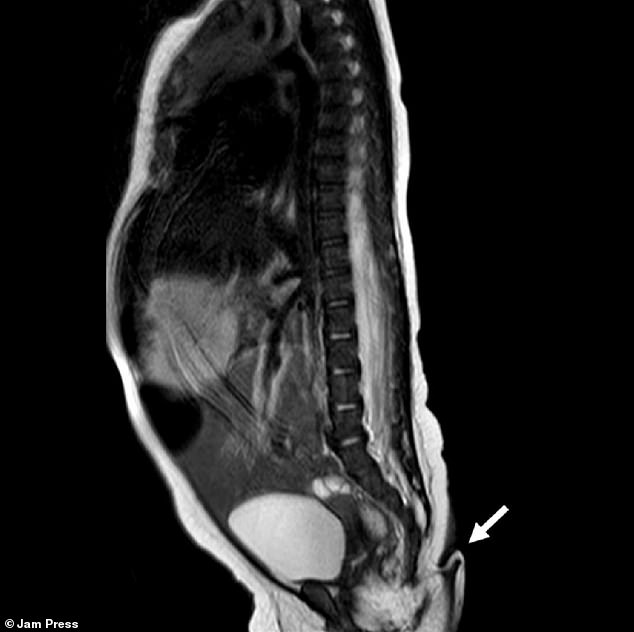

پزشکان میگویند این دختر مکزیکی از نظر سایر اندامها از جمله مغز، قلب، کلیه و حس شنوایی سالم بود. همچنین، اسکنهای پزشکی نشان داد که این دم نتیجه مشکلی در ستون مهرهها مثل دیسرافیسم نبود؛ این بیماری باعث میشود مهرهها بهدرستی شکل نگیرند و در پایین ستون آنها زائدهای شبیه دم رشد پیدا کند.